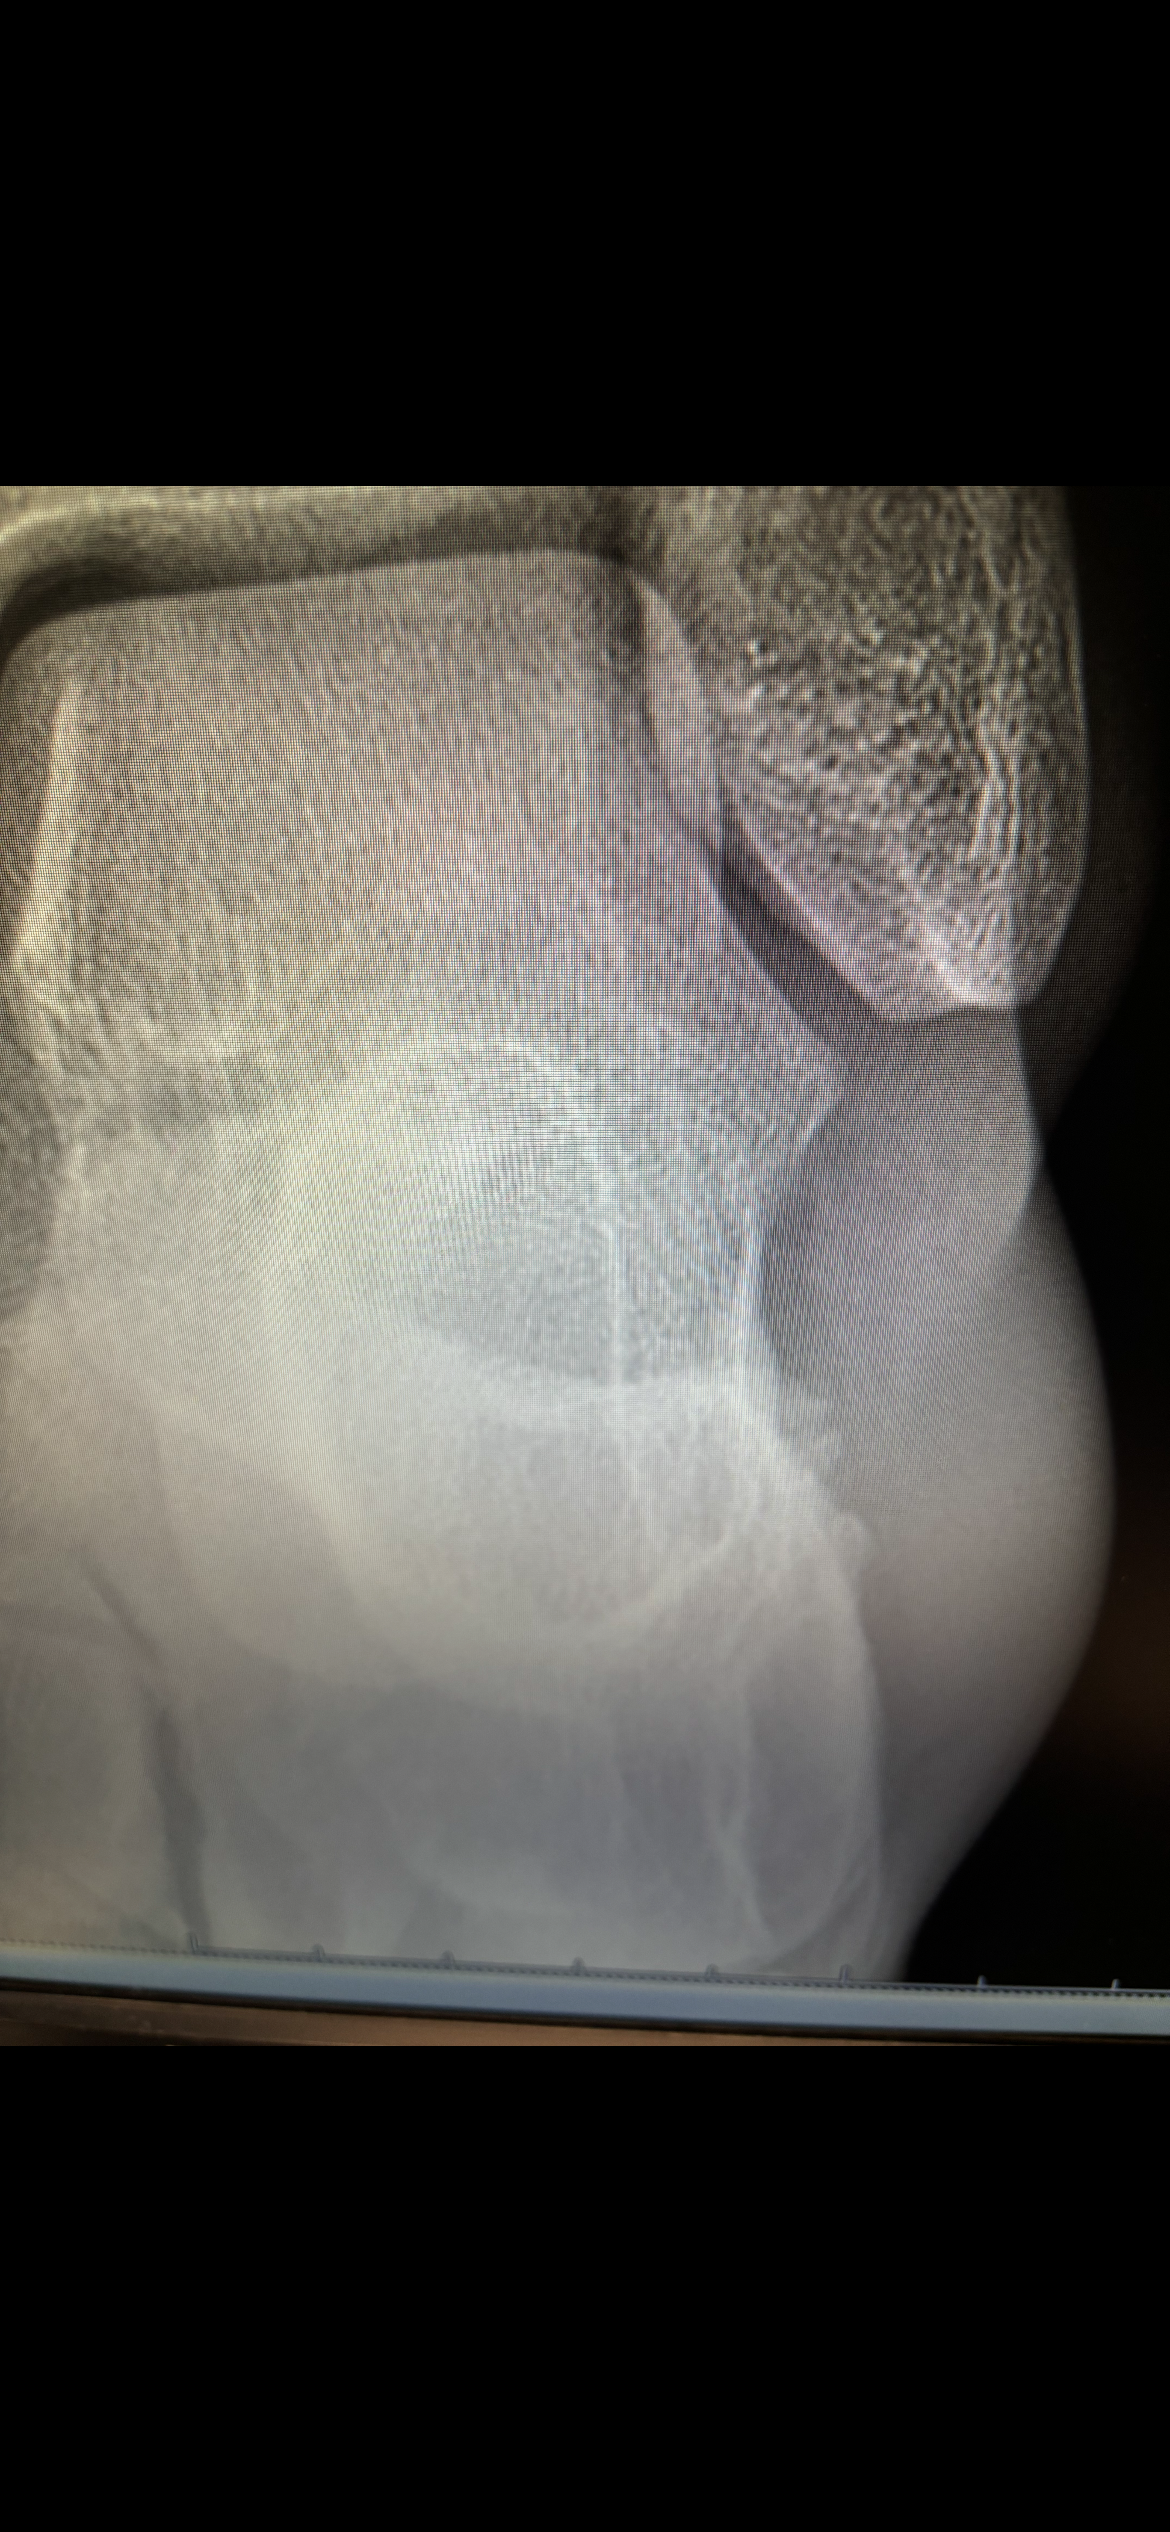

Brett is facing a significant challenge. A foot injury has left him unable to work for 4 weeks, and his job requires standing for extended periods. As a result, he will experience financial hardship, struggling to pay medical bills and cover essential expenses. Any donation, regardless of size, is welcome. Brett is not only my son's best friend but also a kind and supportive individual who has been there for my son during times of need. As a mother, I am eager to return the favor and have created this fundraising account to support him.